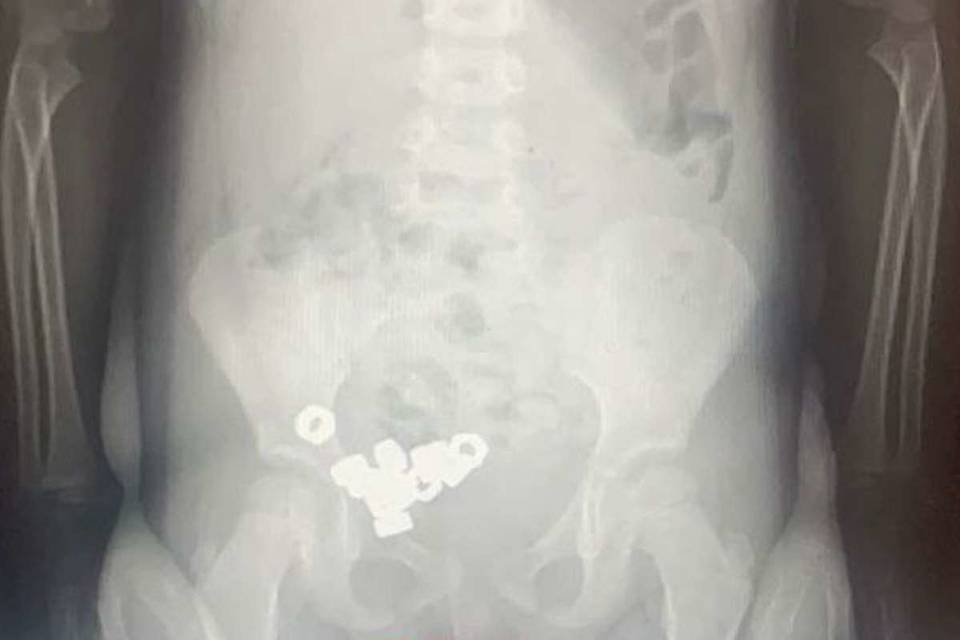

В Воронеже трехлетний ребенок проглотил 16 гаек, сообщает "Обозреватель.Врн".

В приемное отделение мальчика доставили с жалобами от родителей на возможное проглатывание инородных предметов. Рентген брюшной полости показал, что в желудочно-кишечном тракте мальчика действительно находятся 16 маленьких металлических гаек.

Ребенка госпитализировали. Так как инородные тела были не инертные и не магнитные, специалисты выбрали консервативное лечение, назначив пациенту диету, покой, а также контроль стула и рентгенографию в динамике. К счастью, на третий день гайки вышли естественным путем и малыша выписали домой.